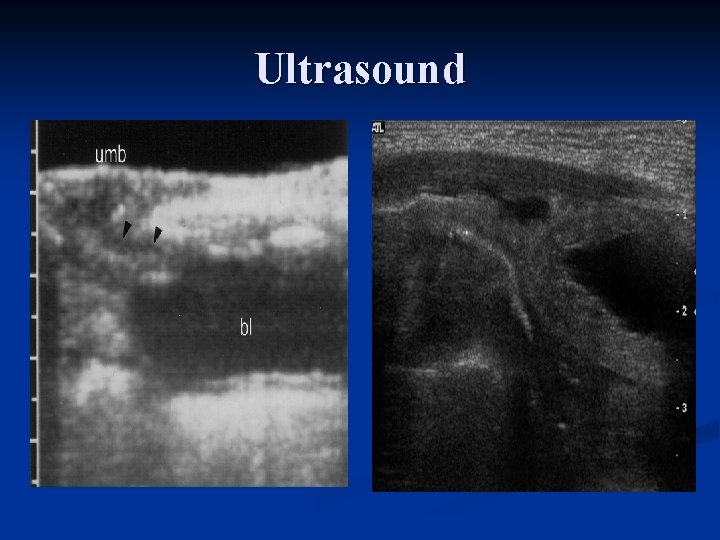

Studies n. Catherization of tract and injection of dye n. Voiding cystourethrogram n. US

Ultrasound